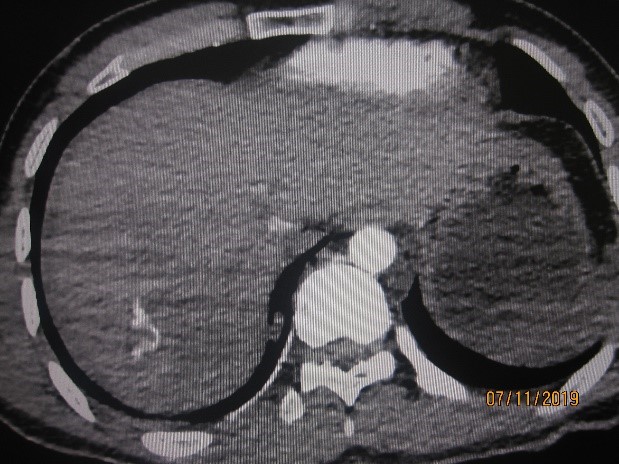

МЕТОДЫ И МАТЕРИАЛЫ. Проанализированы результаты лечения 76 пострадавших с закрытыми травмами печени, получавшим традиционное лечение, и 78, которым лечение проводили в соответствии с разработанным новым алгоритмом. Во второй группе пациентам с УЗИ с признаками разрывов печени и стабильной гемодинамикой (сист. АД>90 мм рт. ст.) выполняли МСКТ с внутривенным контрастированием. При отсутствии признаков продолжающегося кровотечения осуществляли консервативное лечение, при их выявлении – ангиографию с селективной ангиоэмболизацией.

РЕЗУЛЬТАТЫ. Статистически значимых различий по полу, возрасту, механизму и тяжести травмы (по шкалам ISS, Ю. Н. Цибина, ВПХ-П) и тяжести состояния (ВПХ-СП) между пациентами групп не выявлено. Более половины (52,3 %) пострадавших основной группы пролечено без оперативных вмешательств на органах живота. При использовании предложенного алгоритма у пациентов со стабильной гемодинамикой лапароцентез уступил место менее травматичным и более точным методам диагностики внутрибрюшных кровотечений. Все лапаротомии в основной группе были выполнены по поводу других повреждений органов живота. У пострадавших обеих групп видеолапароскопия носила диагностический характер. Одному пациенту основной группы с повреждением печени IV степени по шкале AAST с продолжающимся внутрипаренхиматозным и внутрибрюшным кровотечением проведен эндоваскулярный гемостаз.

3. Рис 2.2

Тема

Тип Исследовательские инструменты

Посмотреть (84KB)

Метаданные ▾